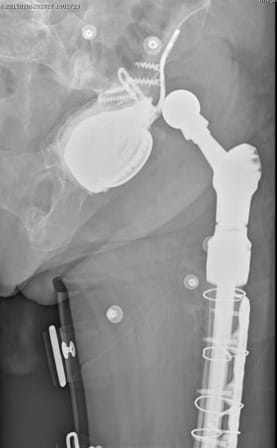

From our perspective, the design of the 3D-printed implant must respect both the dip of the anterior wall and the elevation of the posterior wall. This design is able to reduce anterior and posterior impingement, especially if the orientation of the native acetabulum or the reconstruction imperatives mean fitting the 3D-printed component in a relatively neutral position. The combination with anatomic DM cups is our preferred option. During surgery the relative position of both components must be adjusted in real time (Figure 12).

- Improved management of the restoration of the centre of rotation in the planning stages (Figure 14)